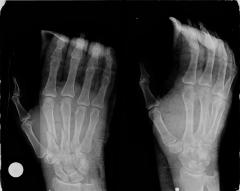

Κατάγματα δακτύλων της άκρας χειρός

Τα εν λόγω κατάγματα είναι συχνά σε νέους ενήλικες, ειδικά χειρώνακτες, καθώς και σε αθλουμένους και μπορεί να είναι μέρος βαρύτερων και πλέον σύνθετων τραυματισμών, που περιλαμβάνουν τένοντες, αγγεία, νεύρα. Οι περιπτώσεις που αντιμετωπίζονται χωρίς χειρουργική επέμβαση είναι λίγες. Ως υλικά οστεοσύνθεσης χρησιμοποιούνται είτε κατάλληλου σχεδιασμού μικρές πλάκες και βίδες είτε λεπτές βελόνες. ΟΙ βελόνες αφαιρούνται πολύ εύκολα μετά από λίγες εβδομάδες, ενώ τα άλλα υλικά παραμένουν και αφαιρούνται χειρουργικώς μόνο εάν χρειαστεί.

Η χειρουργική επέμβαση είναι λεπτή, γίνεται με μεγεθυντικά γυαλιά (loupes) και λεπτά εργαλεία και δεν απαιτεί παραμονή στο νοσοκομείο. Η μετεγχειρητική κινητοποίηση εξαρτάται από τον τύπο του κατάγματος, το είδος της οστεοσύνθεσης αλλά και τυχόν συμπαρομαρτούσες καταστάσεις. Δεν είναι σπάνιο να χρειάζεται περίοδος φυσιοθεραπείας στη συνέχεια.